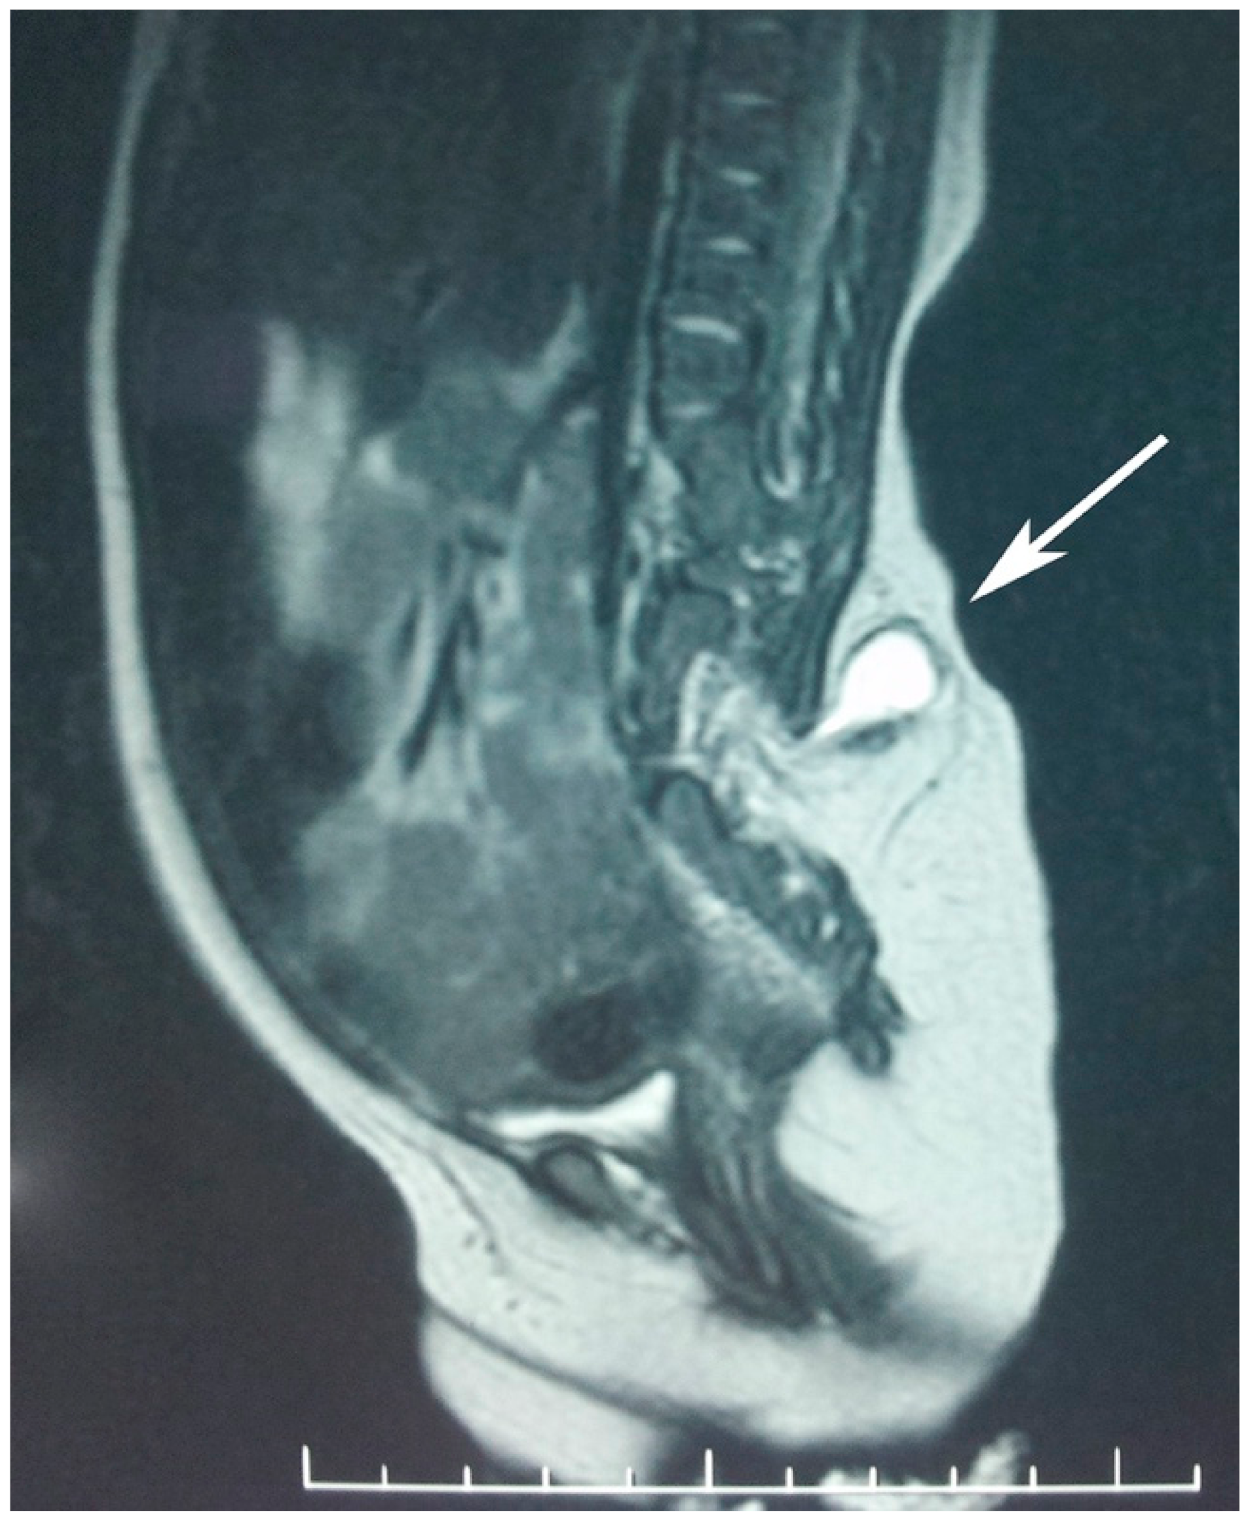

Computed tomography (CT) scan and magnetic resonance imaging (MRI) of the abdomen and pelvis showed a normally structured liver located on the left side together with the portal and superior mesenteric vein. There was malrotation of the left kidney with a horizontal lay, but the right kidney was of normal structure. There was complete duplication of the bladder, with the left on being of a smaller size and each having a well-defined muscular wall. Each kidney and ureter were draining into the ipsilateral bladder. There was an abnormal terminal aorta branching into 3 arteries at the L4 level: the right common iliac artery, left iliac artery, and a median branch with a posterior median pathway. Evaluation of the lumbosacral and pelvic bones revealed type I sacral agenesis: the abnormal fusion of the vertebral bodies was obvious on the anterior side of the lumbar spine region (from L2 to S1 with vertebral body, L1 fused with the L2 hemivertebra, L3 hemivertebra, L4 with two non-fused nuclei, and partial unilateral left agenesis of L5 and sacrum); asymmetry of the hip was due to the higher insertion of the left ilium bone at the malformed lumbosacral spine with a normal coxofemoral left joint. Posterior vertebral fusion abnormalities—lipomyelomeningocele and a tethered spinal cord—were also noted (Figure 4).

In our case the MRI exam demonstrated conus terminalis and cauda equina abnormalities and the relation between the lypomatous tissues and the neural structures. Surgical treatment for type III lypomielomeningocele had the goal of reducing the lipoma and reestablishing the continuity of the meningeal sheets. This will dramatically diminish the risk of the tethered cord syndrome, which is responsible for progressive neurological deficits. In the reviewed cases, including ours, CDS was associated with type I, partial sacral agenesis and a tethered spinal cord image on MRI [2,8] but without spinal cord malformations.

Figure 4. Lipomyelomeningocel, the MRI view (arrow).